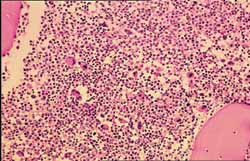

1.周圍血象 主要為白細胞增多,80%在100×109/L以上。血色素在80g/L左右。血小板增多。分類可見粒系增多,包括嗜酸、嗜鹼粒細胞增多。原始粒細胞增多不明顯,以中、晚幼和成熟粒細胞為主。

3.骨髓檢查 增生活躍,以粒系增生為主,原始粒細胞<10%,多為中晚幼粒細胞及桿狀核細胞粒∶紅為10~50∶1。部分患者可見骨髓纖維化。骨髓巨核細胞明顯增多,以成熟巨核細胞為主。骨髓培養集落與叢落皆增多